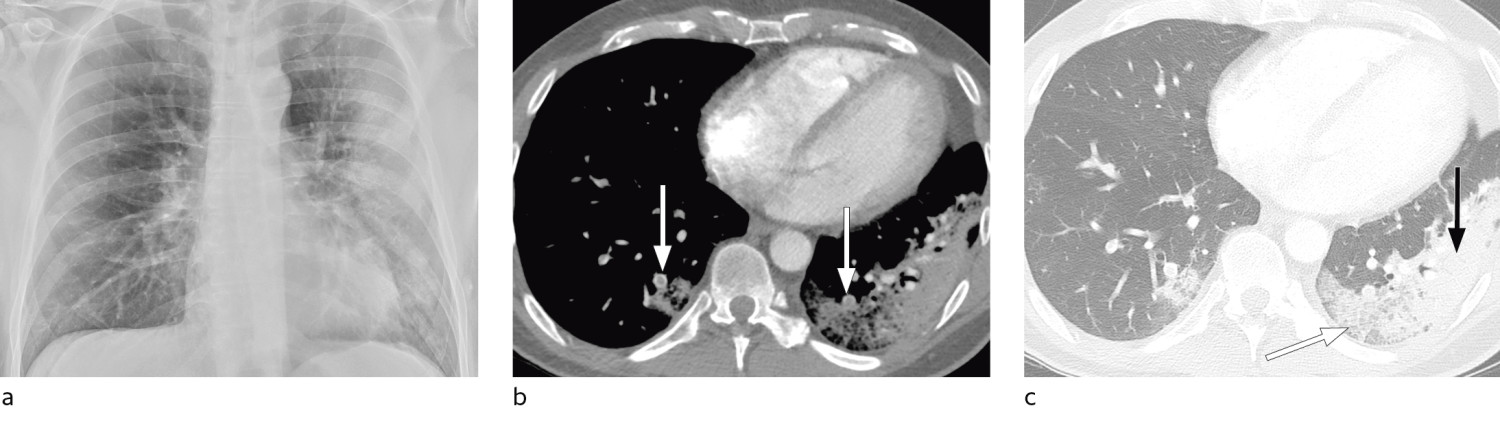

I et materiale fra Hongkong hadde 69 % funn på røntgen thorax før behandling (baseline), men 9 % hadde funn på røntgen thorax før positiv PCR (14). Sensitiviteten for røntgen thorax var 69 % og for PCR 91 %. Vanligste røntgenfunn var bilateral konsolidering og mattglassfortetninger med perifer og kaudal distribusjon. Forandringene var mest uttalt 10–12 dager etter symptomdebut. Figur 1 og figur 2 viser typiske funn på røntgen thorax ved covid-19.

Hos inneliggende pasienter kan et sengebilde i tidlig stadium være nyttig som sammenligningsgrunnlag for tolking av bilder tatt senere. Hos pasienter med alvorlig sykdom vil det være indisert med sengebilder for kontroll av medisinskteknisk utstyr (figur 3), men det er ikke indisert med daglig, rutinemessig røntgen thorax hos stabile pasienter. I forløpet av sykdommen vil det være indisert med sengebilde ved mistanke om komplikasjoner og ved oppfølging og monitorering av sykdomsprogresjon.

Typiske CT-funn varierer med symptomvarighet og kan deles i tre stadier: en tidlig fase, en intermediær fase som strekker seg fra 3–5 dager etter symptomdebut, og en senfase. Det er ikke alltid funn på CT de første dagene etter symptomdebut. I et materiale med symptomatiske, men uspesifiserte pasienter hadde 56 % normale funn på CT innen to dager etter symptomdebut (12), avtakende til 9 % 3–5 dager etter symptomdebut og 4 % 6–12 dager etter symptomdebut. Funnhyppighet varierer med sykdommens alvorlighetsgrad. Ved første gangs bildediagnostikk var det normale funn hos 18 % i en gruppe pasienter med ikke alvorlig sykdom, men hos bare 3 % av pasienter med alvorlig sykdom (15). Typiske CT-funn er multiple, bilaterale mattglassfortetninger med perifer distribusjon, hyppigst lokalisert i underlappene. I intermediær fase er det økende innslag av konsolidering (tette infiltrater) og affeksjon av flere lapper samt økt septering med brosteinsmønster (crazy paving) som tegn på interstitiell affeksjon. I senfasen er det økende total utbredelse, men mattglassfortetninger og konsolidering er fremdeles dominerende funn (12, 16). Figur 4, figur 5 og figur 6 viser typiske funn på CT i ulike faser av covid-19.